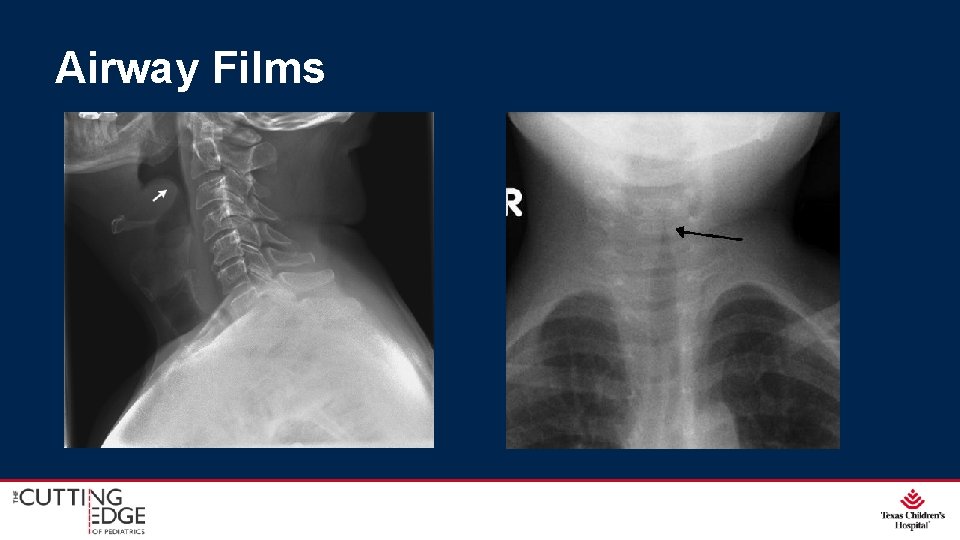

Airway Films